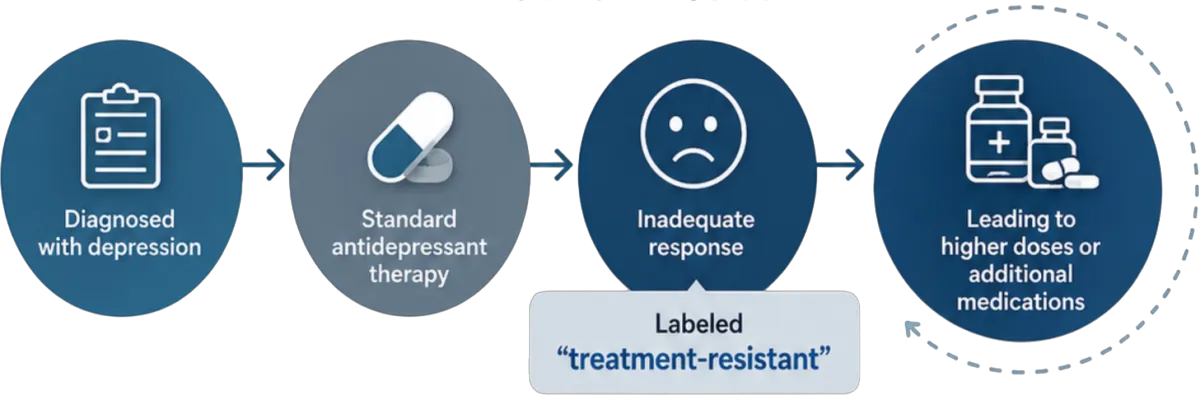

Emerging evidence suggests something important:

In many of these patients, the issue may not originate in brain chemistry alone.

Instead, it may involve dysfunction in the autonomic nervous system—the system responsible for regulating the body’s most critical moment-to-moment functions, including heart rate, blood pressure, and cerebral blood flow.

The brain does not function in isolation.

It depends on stable physiological regulation to receive consistent oxygen and nutrient delivery.

When autonomic function is impaired:

Cerebral blood flow can become inconsistent

Oxygen and nutrient delivery may be disrupted

Neurological performance can decline

This raises a critical question for providers:

If the underlying issue is dysregulation… can symptom-based treatment alone resolve it?